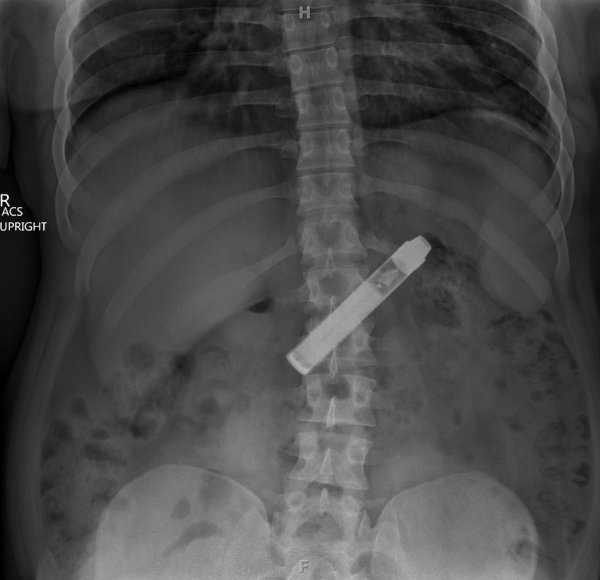

Специалисты по рентгеновской диагностике регулярно сталкиваются с посторонними предметами внутри тела человека. Обычно лишние предметы попадают в пищеварительную систему из-за неосторожности при еде или во время неудачных любовных игр. Почти всё удается вытащить — с хирургическим вмешательством или без него. выбрал самые необычные находки радиологов, которыми они делились на сайте Radiopaedia.org.